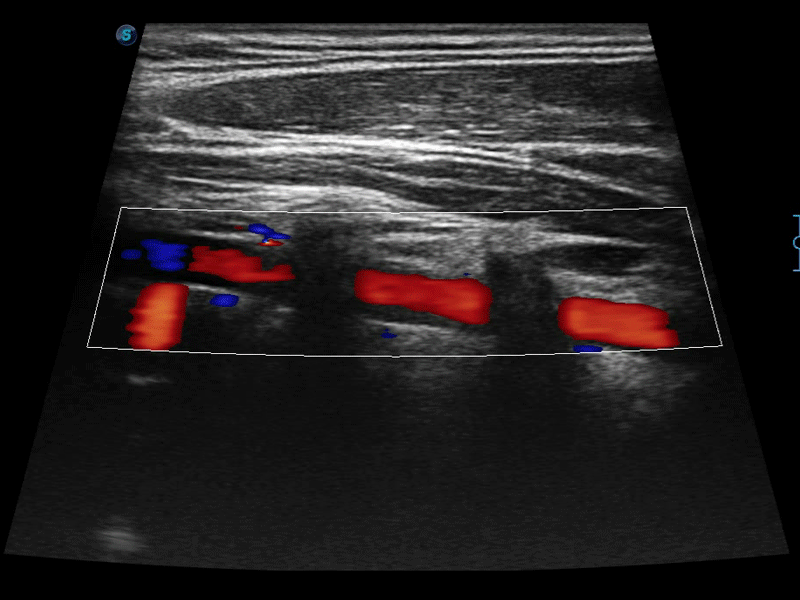

高分辨率血流成像技術提高了對低速血流信號的檢測能力。在提高空間分辨率的同時,也克服了血流外溢現象,為用戶提供更加真實的血流動力學信息。

通過色彩血流和實時寬景相結合,可觀察到完整的靜脈或動脈的血流,方便醫(yī)生檢查。實時掃查過程中,如有任何操作失誤也可以很容易地進行回掃擦除,而不會中斷掃查。